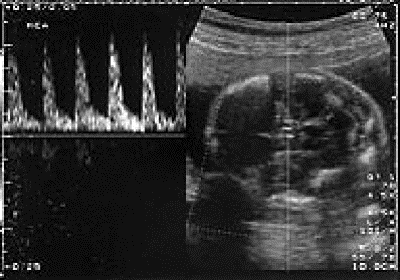

beremennost-echo-05